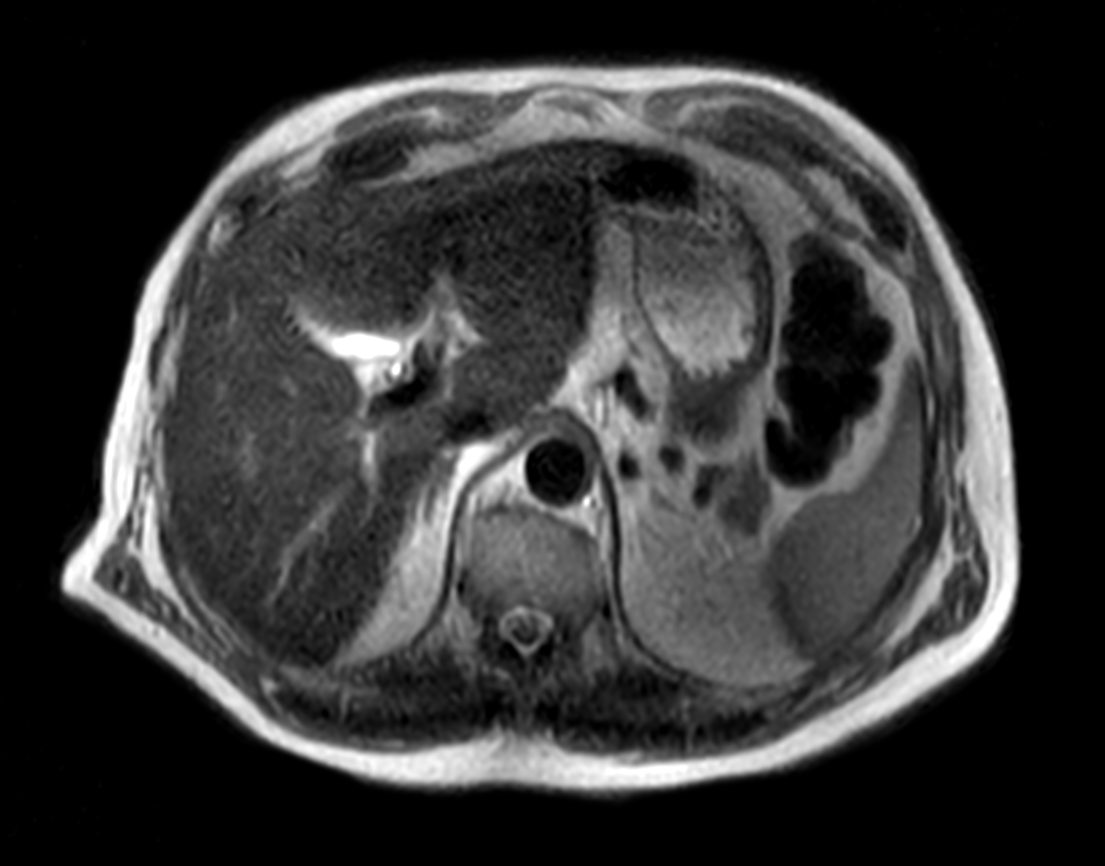

Multi Nuclei - Liver imaging (13C)

Make multi-nuclei imaging and spectroscopy become part of your clinical operations via a seamless integrated workflow for multi-nuclei image acquisition, spectroscopy, reconstruction, and viewing. The nucleus is just a scan parameter like any other sequence parameter. A single ExamCard can be used to run both proton and non-proton imaging. Reconstruction and viewing of non-proton images or spectra, as well as the process for sending the data to PACS is fully integrated, so workflow does not differ from proton imaging. The transmit-receive 13C flex coil, with a 14 cm diameter, is immediately recognized by the ExamCard interface. Improved SNR and simplified spectra* are achieved by combining body coil decoupling with the transmit-receive surface coils.